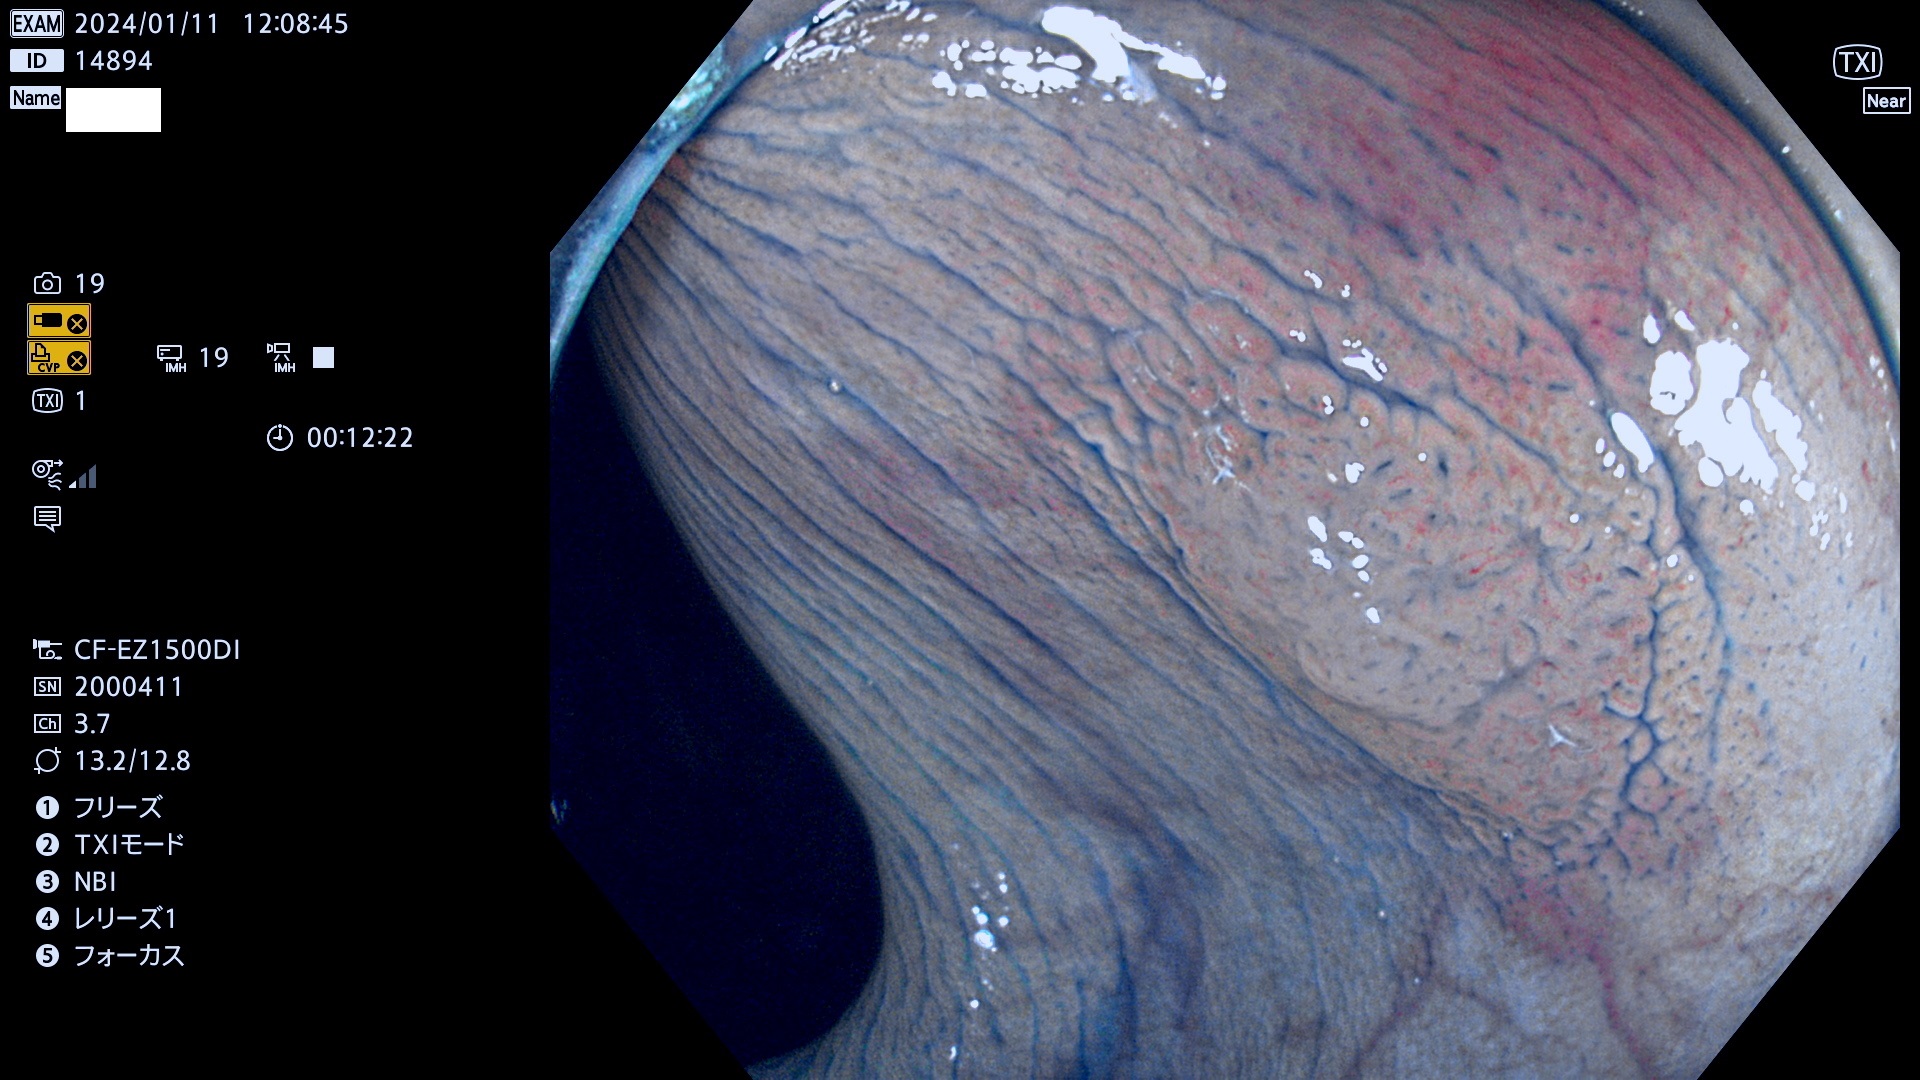

表面型腺腫(Flat Adenoma)の中で、完全に平坦な物をUb、陥凹している物をUcと呼びます。平坦隆起型(Ua)よりも、発見が難しく危険な病変です。

毎週の検査(木・金・土・日)に発見されたUb、Uc型・腺腫を、その週の日曜の夜にUPし1週間、提示します。

抽出の対象期間 2024年1月11日(木))〜1月14(日)の4日間(40件の検査)9件